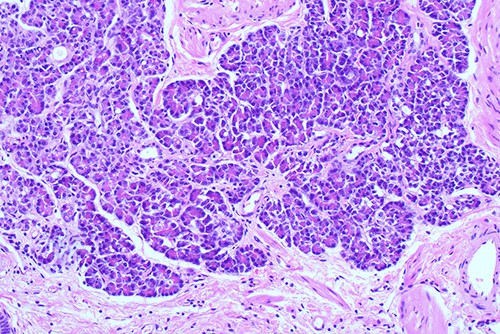

Histological examination of gallbladder ×20 showing island of ectopic pancreatic tissue adjacent to the mucosa of the gallbladder neck.

Histological examination of gallbladder ×40 showing island of ectopic pancreatic tissue adjacent to the mucosa of the gallbladder neck.